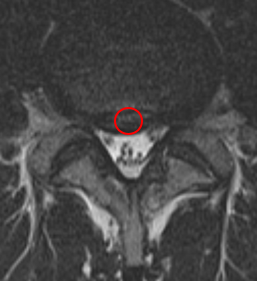

診察と検査結果

この患者様は赤い枠で示されている箇所に椎間板ヘルニア(L4/5)が認められます。